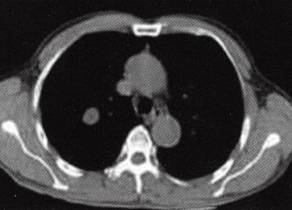

图1肺错构瘤

C

C.纵隔窗示结节内多个点条状钙化,中心斑点状脂肪样密度区;

(1)病灶直径多<2.5 cm,边缘光滑,可浅分叶。 (2)病灶密度不均匀,可见短条状钙化,典型征象为“爆米花样”钙化,部分见脂肪密度影。 (3)增强扫描病灶无明显强化。 2)中央型: (1)支气管腔内结节,边缘光整,可见钙化。 (2)附着处支气管壁无侵蚀增厚。 (3)远端支气管阻塞性肺炎和/或肺不张改变。 4.MRI表现: 周围型结节显示信号不均勻,脂肪成分显示优于CT,可确诊。影像学检查显示肺周围境界光整的孤立性结节,见有“爆米花样”钙化或脂肪组织即可确诊。 【分析思路】 诊断依据: 1.患者为男性,63岁。无症状,偶然发现。 2.右肺孤立性结节,边缘光滑,无分叶,结节内多个点条状钙化,有脂肪样密度影,增强扫描病灶无明显强化。 3.无肺门、纵隔淋巴结增大及胸腔积液。 鉴别诊断: 1.周围型肺癌:①多为大于3 cm的肿块。②结节型多边缘毛糙,见“短毛刺征”“分叶征”。③病灶密度多不均勻,可见“空泡征”。④偶见点状钙化。增强多为明显强化。⑤本例结节灶未见肺癌常见征象,也未见肺门及纵隔淋巴结肿大、胸腔积液,所以不符合肺癌影像学表现。 2.结核球:①多位于两上肺。②结节灶单发多见,边缘锐利,无分叶,多有钙化等良性征象。③结核结节周围常见“卫星灶”,结节中央干酪样坏死密度低,钙化为点簇、层环样表现,增强如有强化则多呈环状强化。④本例结节内钙化形态呈短条样且见脂肪密度影,病灶周围肺野清晰,所以不支持结核球诊断。 3.肺内其他良性肿瘤:①与此例类似征象如:结节灶光整,无分叶。②无此例结节灶内所见钙化形态、数量和脂肪样密度征象,所以不考虑其他罕见良性肿瘤诊断。 4.肺动静脉瘘:①与此例类似征象如:孤立结节、边界光整、无分叶。②动静脉瘘增强扫描可见特征性的病灶明显强化及引流血管影征象,所以不符。